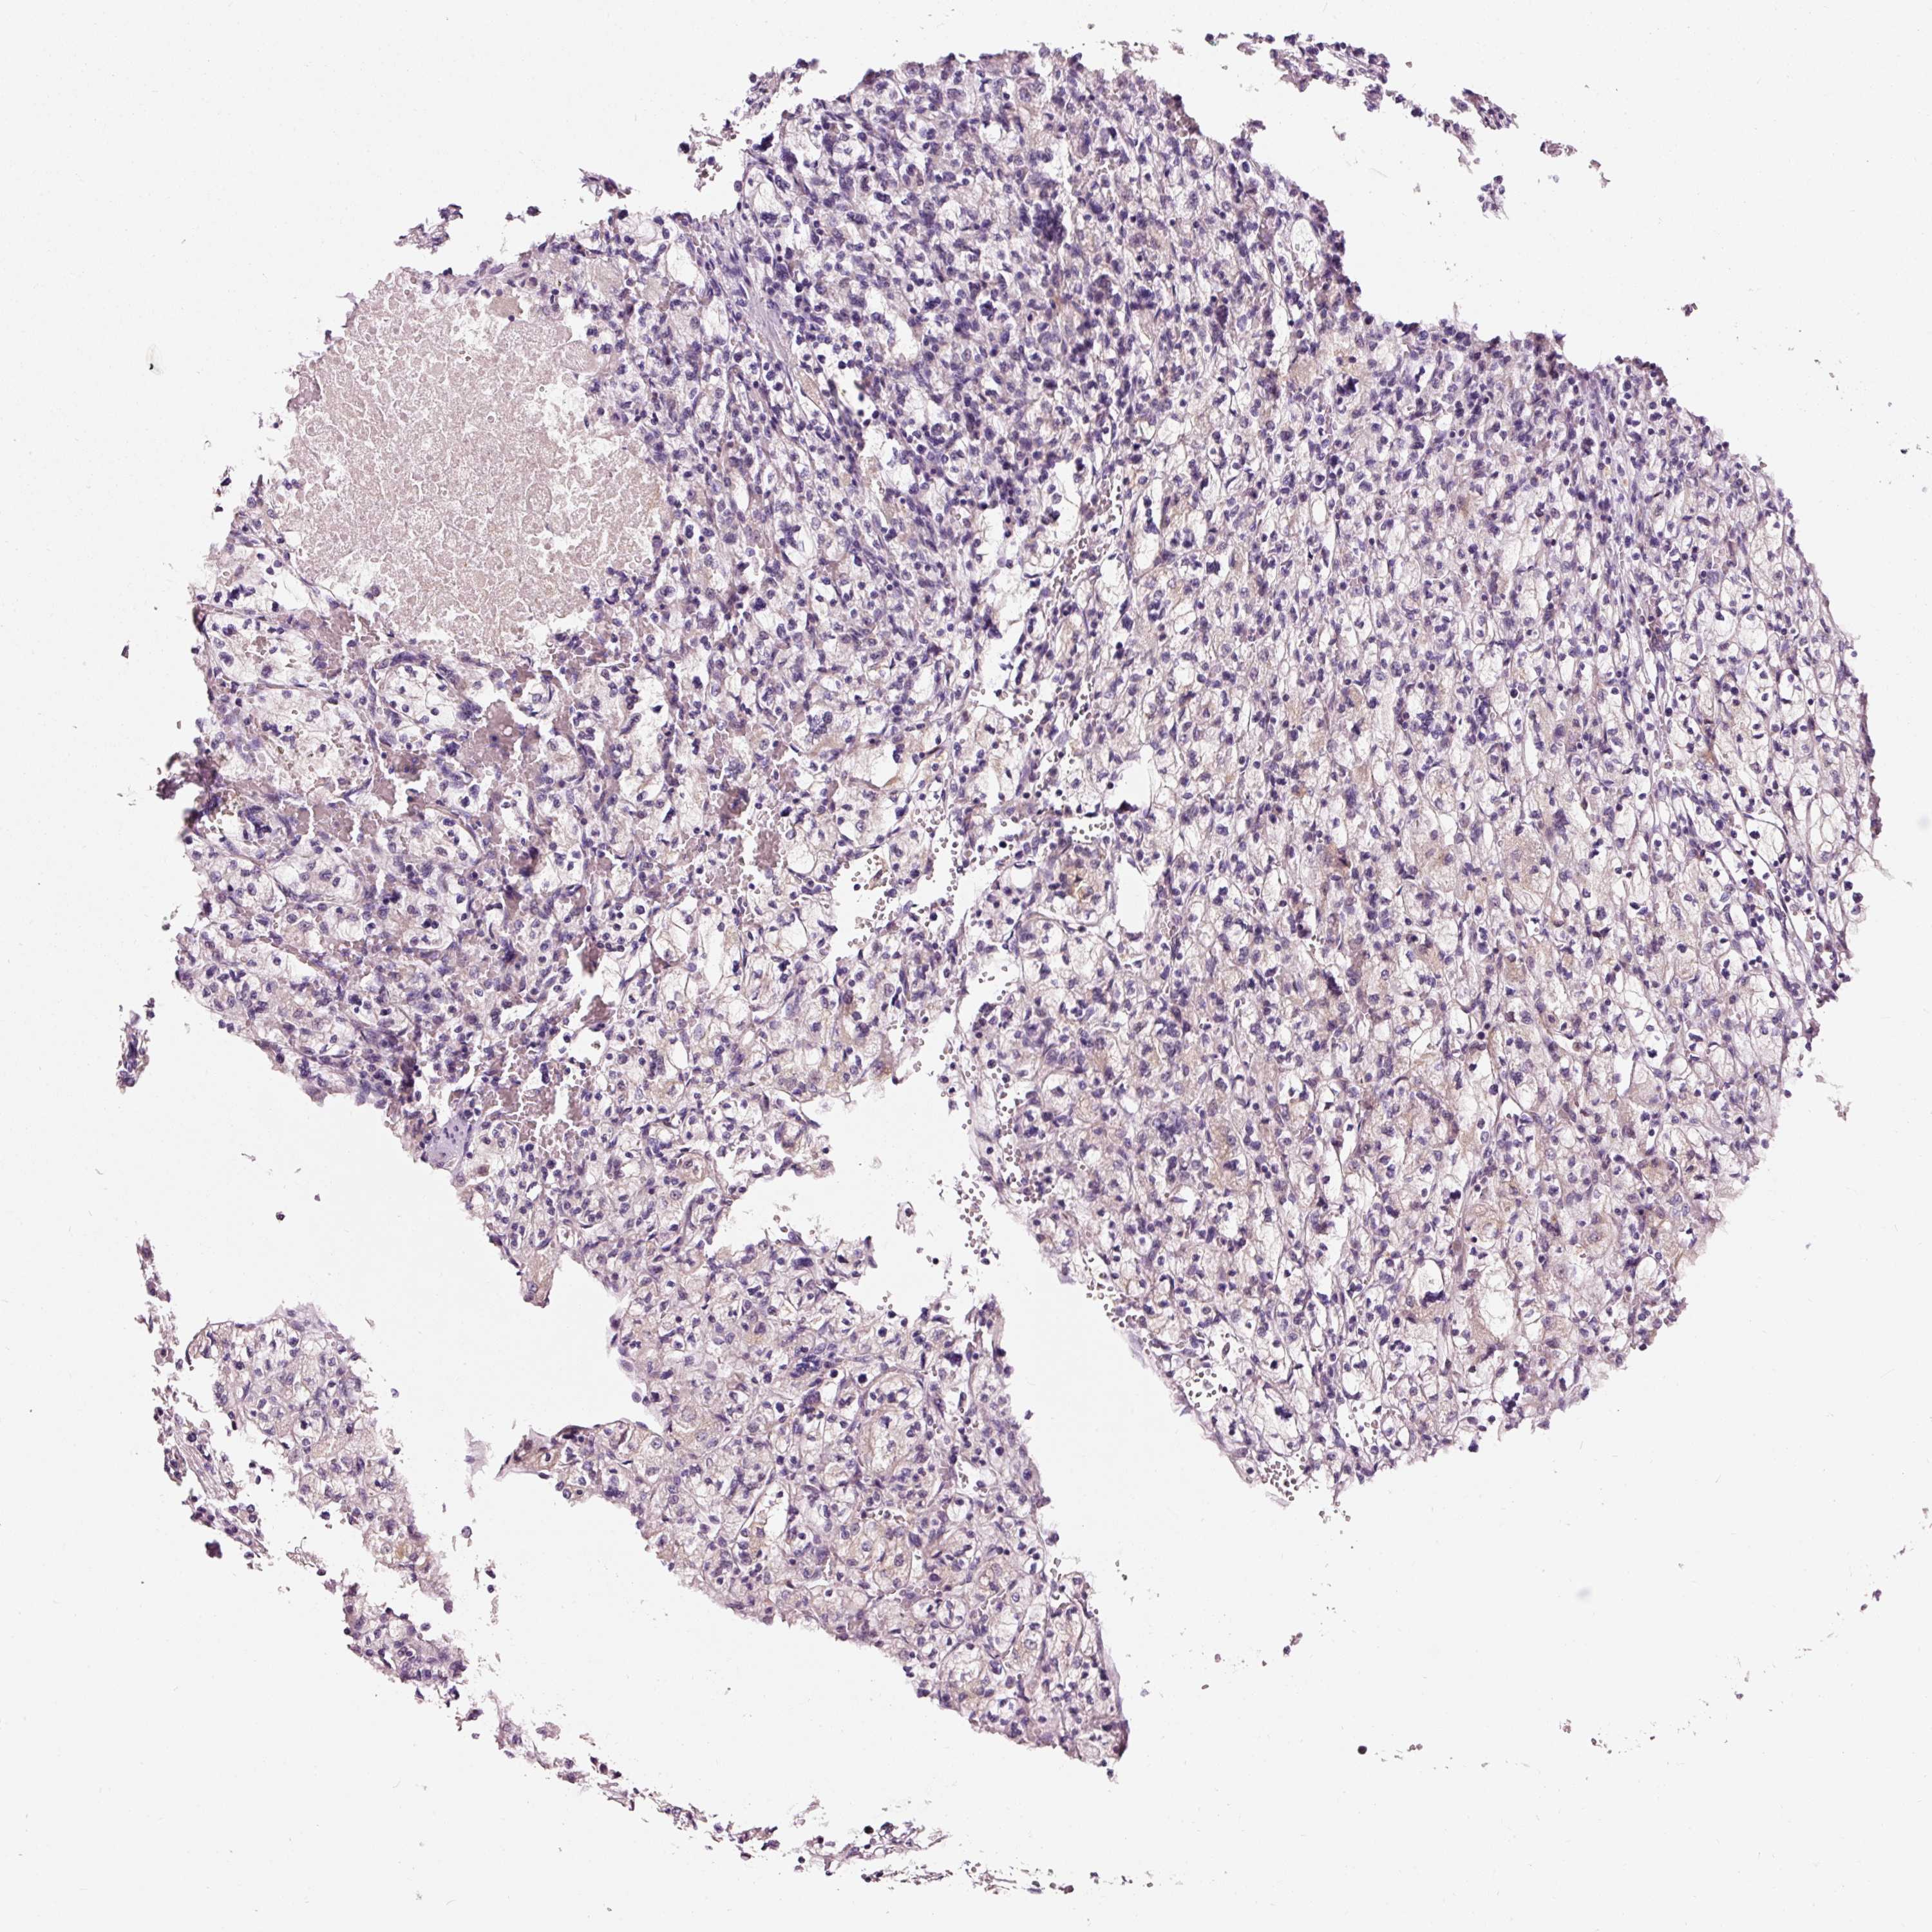

KIDNEY RENAL CLEAR CELL CARCINOMA (VALIDATION) - Interactive survival scatter ploti

The Survival Scatter plot shows the clinical status (i.e. dead or alive) for all individuals in the patient cohort, based on the same data that underlies the corresponding Kaplan-Meier plots. Patients that are alive at last time for follow-up are shown in blue and patients who have died during the study are shown in red.

The x-axis shows the expression levels (FPKM) of the investigated gene in the tumor tissue at the time of diagnosis. The y-axis shows the follow-up time after diagnosis (years). Both axes are complimented with kernel density curves demonstrating the data density over the axes. The top density plot shows the expression levels (FPKM) distribution among dead (red) and alive patients (blue). The right density plot shows the data density of the survived years of dead patients with high and low expression levels respectively, stratified using the cutoff indicated by the vertical dashed line through the Survival Scatter plot. This cutoff is automatically defined based on the FPKM cutoff that minimizes the p-score. The cutoff can be changed by dragging the vertical line or by entering a cutoff value in the square labeled "Current cut-off".

Under the Survival Scatter plot the p-score landscape (black curve; left axis) is shown together with dead median separation (red curve; right axis). Dead median separation is the difference in median mRNA expression between patients who have died with high and low expression, respectively. It is calculated as follows: median FPKM expression of dead patients with high expression - median FPKM expression of dead patients with low expression. This is intended to aid the user in visually exploring custom cutoffs and the associated p-scores and dead median separation.

Individual patient data is displayed and can be filtered by clicking on one or more of the category buttons on the top of the page. Categories describing expression level and patient information include: high, low, alive, dead, female, male and tumor stages. The scale of the x-axis can be toggled between linear and log-scale by clicking on the "x log" button. Mouse-over function shows TCGA ID, patient information and mRNA expression (FPKM) for each patient.

& Survival analysisi

Kaplan-Meier plots summarize results from analysis of correlation between mRNA expression level and patient survival. Patients were divided based on level of expression into one of the two groups "low" (under cut off) or "high" (over cut off). X-axis shows time for survival (years) and y-axis shows the probability of survival, where 1.0 corresponds to 100 percent.

NAPA is not prognostic in Kidney Renal Clear Cell Carcinoma (validation)

Best expression cut offi

Based on the FPKM value of each gene, patients were classified into two groups and association between prognosis (survival) and gene expression (FPKM) was examined. The best expression cut-off refers the FPKM value that yields maximal difference with regard to survival between the two groups at the lowest log-rank P-value. Best expression cut-off was selected based on survival analysis .

When clicking on this number, the vertical dashed line indicating cut-off, the interactive survival plot, and the Kaplan-Meier curve will be adjusted to show results based on the best expression cut-off.

: 90.25

Average pTPM 103.0

Number of samples 100